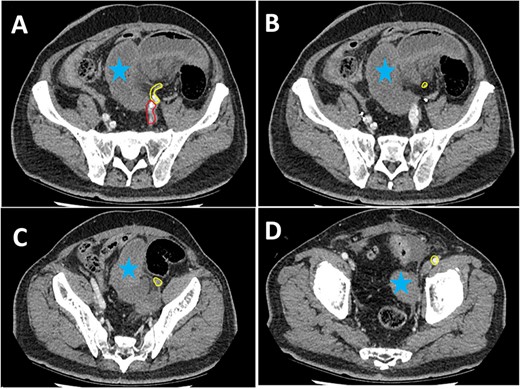

Series of axial images of initial CT progressing from most superior (image A) to inferior (image D). The EIA has been highlighted in yellow from immediately inferior to the bifurcation of the common iliac artery. The internal iliac artery can be seen in red in image A. Images B and C demonstrate a collapsed EIA between dilated loops of small bowel suggesting involvement in the internal hernia. Image D demonstrates opacification of the EIA indicating flow distal to the internal hernia. Dilated loops of bowel have been marked with a blue star.

Pre-operative identification of internal hernias would allow for optimal management and planning, however diagnosis of intestinal herniation causing SBO on imaging can be challenging. CT features such as atypical bowel configuration, mesenteric abnormalities (including displacement, twisting or stretching of mesenteric vessels) and the position of surrounding viscera raise the index of suspicion of internal herniation [13]. In this case, retrospective review of the CT scan demonstrates the proximity and compression or partial occlusion of the segment of EIA within the closed-loop obstruction (Figs 3 and 4). This is concordant with our intra-operative findings of a narrow, non-pulsatile structure.